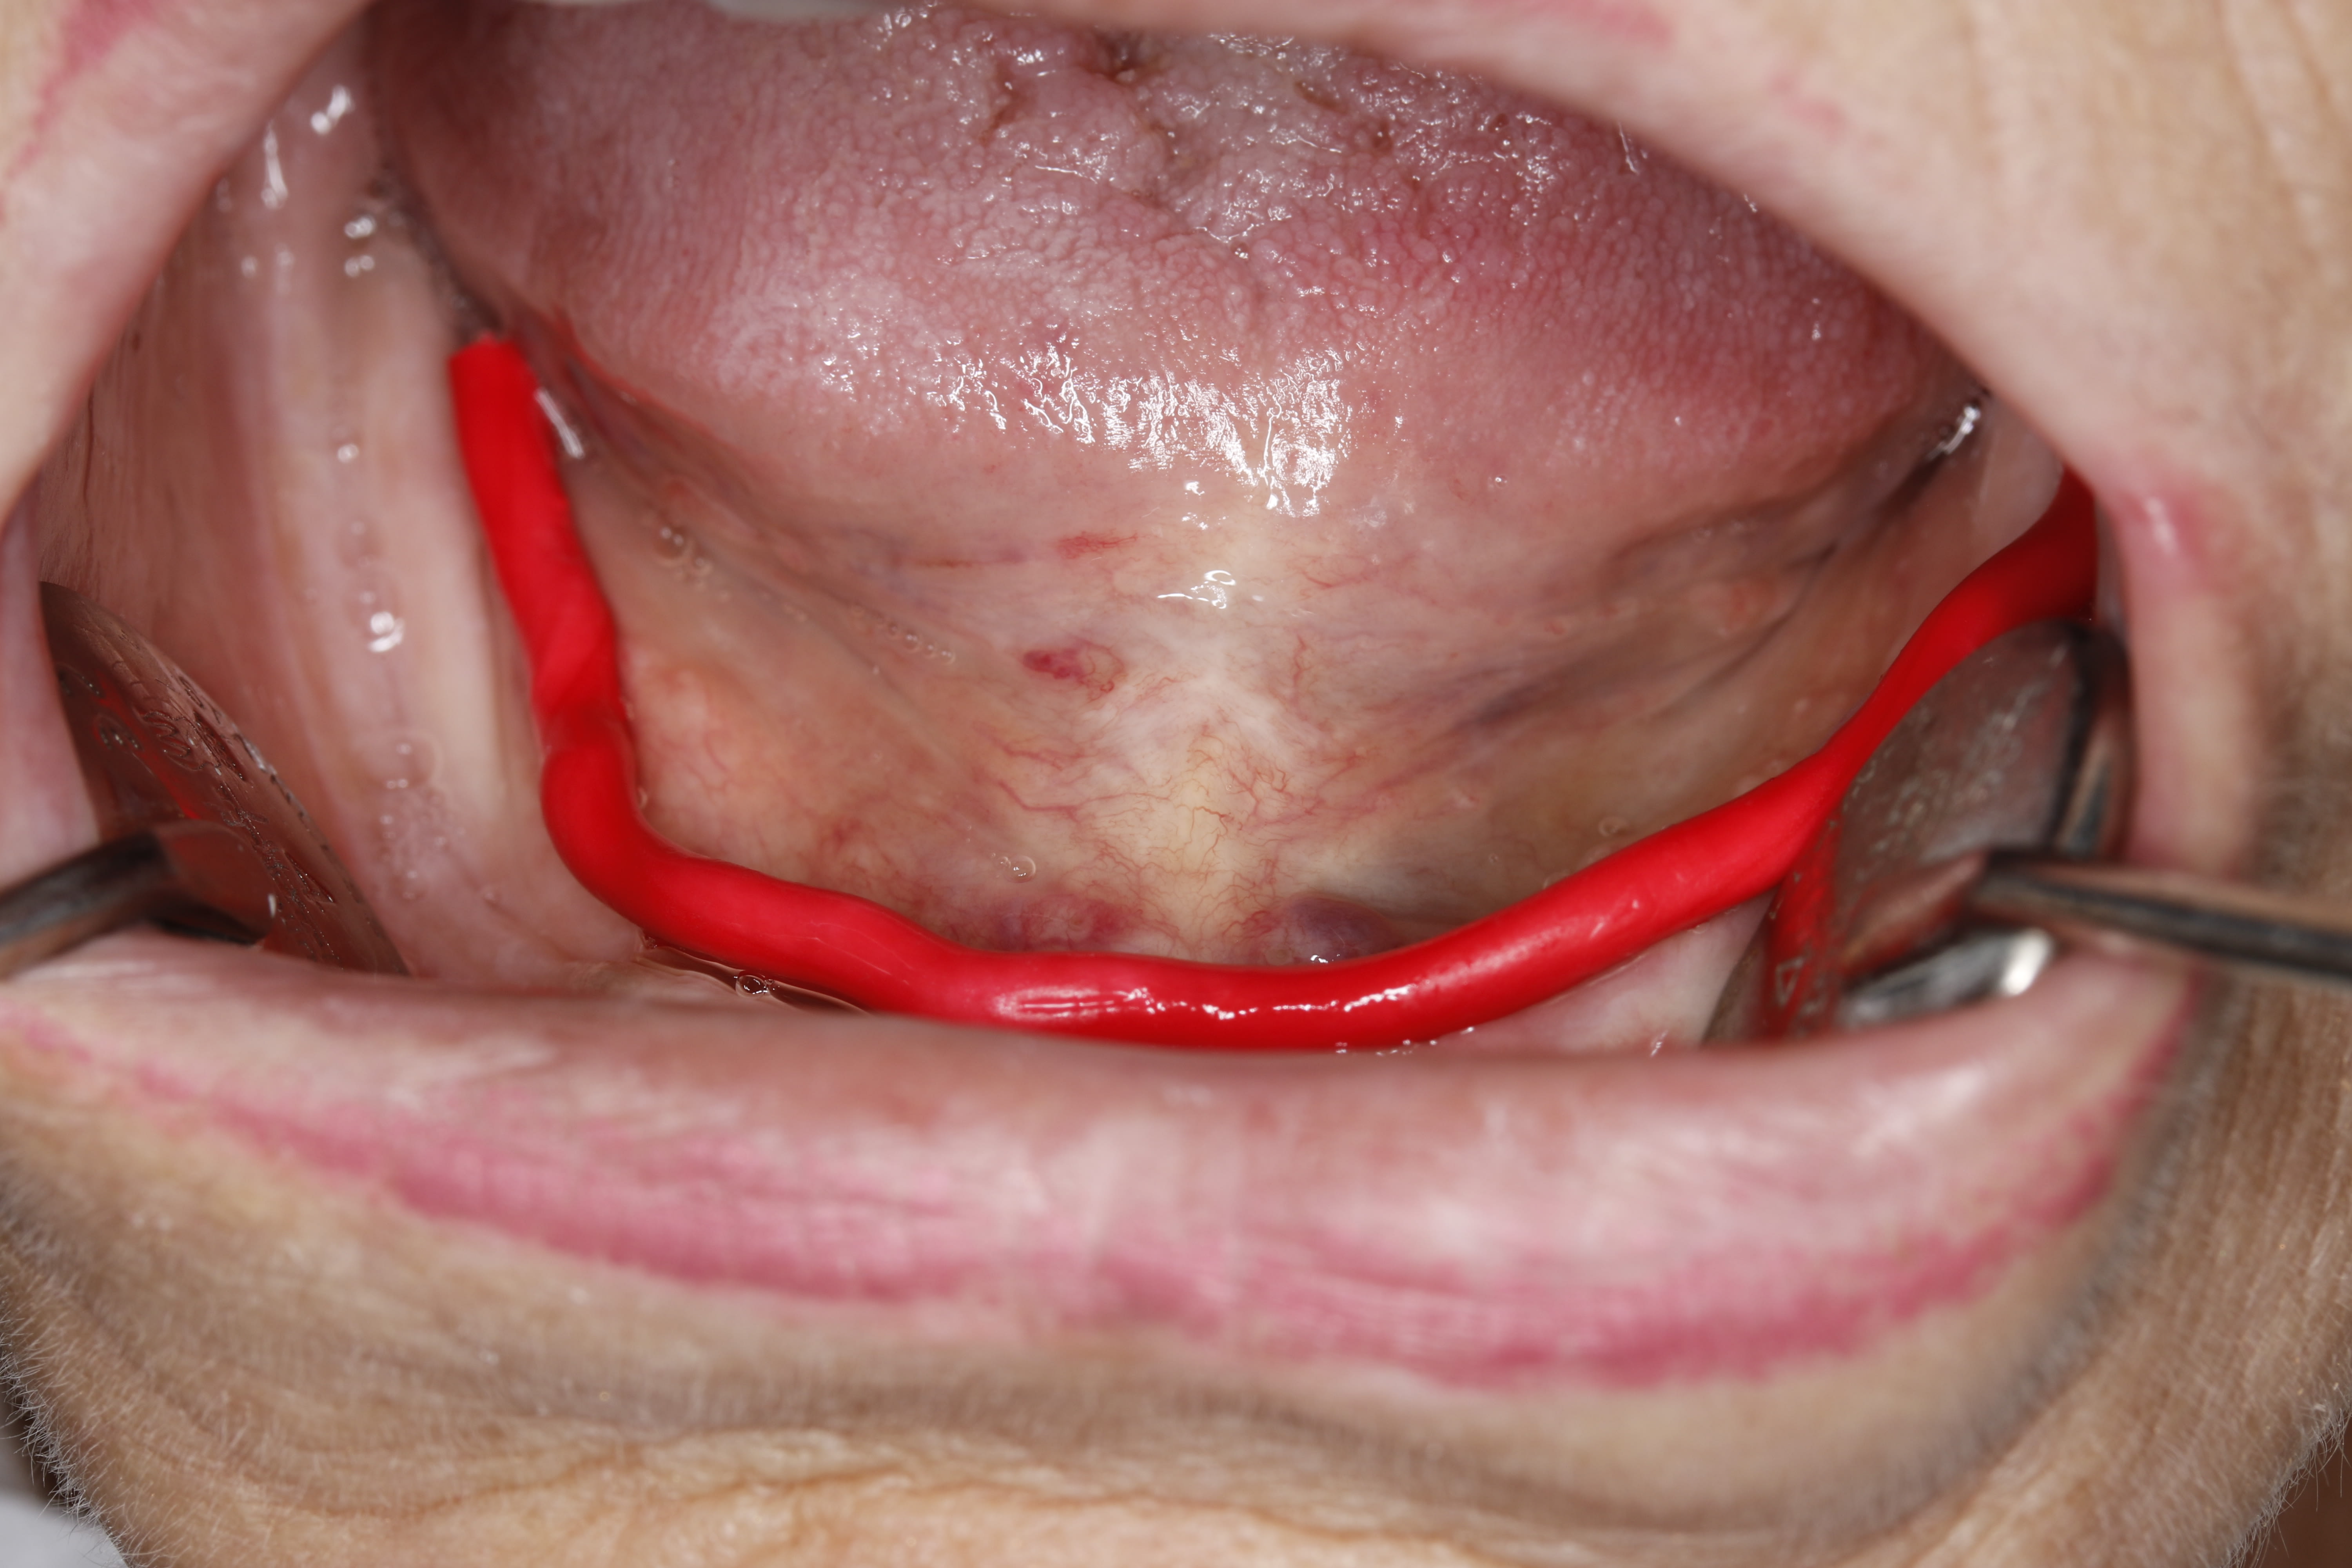

Regardez moi cette lésion trouvée sur un patient porteur de complet :

https://www.dropbox.com/s/i5gkj0y5s8dkzyx/IMG_0596.JPG?dl=0

C'est un garçon ...

On avait eu un post il y a pas longtemps, c'était plutôt feminin.